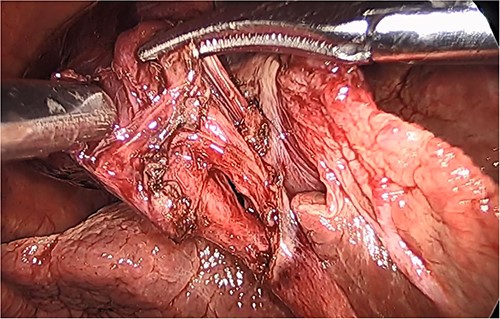

She had a good functional baseline, living in home independently and following anaesthetic review; after a family discussion, the consensus was to proceed to surgery. She underwent a laparoscopic cholecystectomy, and intraoperatively, the diagnosis of gallbladder volvulus was confirmed. A distended gangrenous gallbladder was found, which had undergone 360° clockwise rotation about the cystic duct (Figs 2, 3). The gallbladder was detorted to facilitate a traditional dissection of Calot’s triangle, achieving the critical view of safety (Figs 4, 5). The cystic duct was able to be cannulated facilitating an intraoperative cholangiogram which was unremarkable (Fig. 6). The gallbladder was then removed, and operation was completed without any complications. The histopathology of the gallbladder found diffuse haemorrhagic necrosis of the gallbladder without any evidence of dysplasia or malignancy. No cholelithiasis was present.

Gallbladder after being un-torted, showing the long cystic pedicle.